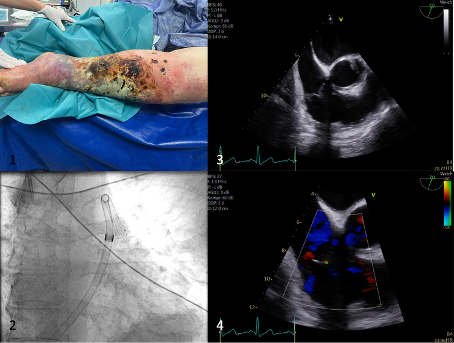

Abbildung 1: 1) Klinischer Befund der nektrotisierenden Fasziitis des linken Unterschenkels 2) einliegender 18-Fr- AlphaVac- Katheter im Truncus Pulmonalis (RAO Kranial) 3 + 4) modifizierter RV- Inflow im Follow View im TEE ohne nachweisbare Rechtherzbelastung – weitere Bilder folgen bei Fallpräsentation.

Fall Präsentation: Ein 50-jähriger Patient ohne Vorerkrankungen stellte sich über den Schockraum nach Synkope und mit zunehmenden Schmerzen im rechten Unterschenkel vor. Er imponierte septisch und hämodynamisch instabil. Klinisch zeigte sich eine nekrotisierende Fasziitis des rechten Beins mit Indikation zur sofortigen Amputations-OP. Das Polytrauma-Spiral-CT zeigte ,,nebenbefundlich‘‘eine Lungenembolie mit totaler Okklusion der rechten Pulmonalarterie und ausgeprägter Rechtsherzbelastung. Im Rahmen der Amputations-OP kam es dann zu konsekutiver hämodynamischer Instabilität. Noch im OP- Saal erfolgte daher eine interventionelle mechanische Thrombus-Aspiration mittels 18-Fr-Aspirationskanüle (AlphaVac-Systems). Die Prozedur verlief komplikationslos und stabilisierte den Patienten unmittelbar. Die Rechtsherzbelastung und der Katecholaminbedarf reduzierten sich signifikant. Im Follow Up zeigte sich ein unauffälliger echokardiografischer Befund ohne Zeichen einer Rechtsherzbelastung. Der Patient konnte in gutem Allgemeinzustand das Krankenhaus verlassen.